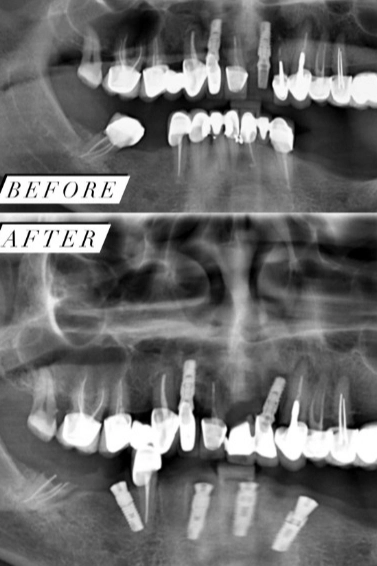

Ο Αλεβίζος Άκης είναι Χειρουργός Οδοντίατρος, Εμφυτευματολόγος και διατηρεί ιδιωτικό οδοντιατρείο στη Νέα Ιωνία. Είναι απόφοιτος της Οδοντιατρικής Σχολής του Εθνικού και Καποδιστριακού Πανεπιστημίου Αθηνών και κάτοχος μεταπτυχιακού τίτλου σπουδών στη "Στοματική Χειρουργική και Εμφυτευματολογία" από το UCAM Catholic University of Murcia στην Ισπανία. Στην επαγγελματική του πορεία μέχρι και σήμερα, υπηρετεί ως αξιωματικός του Πολεμικού Ναυτικού και διατελεί Στρατιωτικός Χειρουργός Οδοντίατρος στο Ναυτικό Νοσοκομείο Αθηνών, καθώς και στο Οδοντιατρικό Κέντρο του Πολεμικού Ναυτικού. Εξειδικεύεται στην Αισθητική Οδοντιατρική, αναλαμβάνοντας περιστατικά που αφορούν θήκες, λεύκανση δοντιών, όψεις ρητίνης και πορσελάνης, καθώς και χειρουργικά περιστατικά, όπως έγκλειστοι φρονιμίτες, εκτομή χαλινού με laser και θεραπεία περιοδοντίτιδας. Στο ιδιωτικό οδοντιατρείο του, έναν χώρο άρτια εξοπλισμένο με τα πιο σύγχρονα μηχανήματα για ενδοδοντικές θεραπείες, παρέχει υπηρεσίες σε όλο το φάσμα της Οδοντιατρικής, δίνοντας ιδιαίτερη έμφαση στην πρόληψη και στην αποτελεσματική αποκατάσταση.